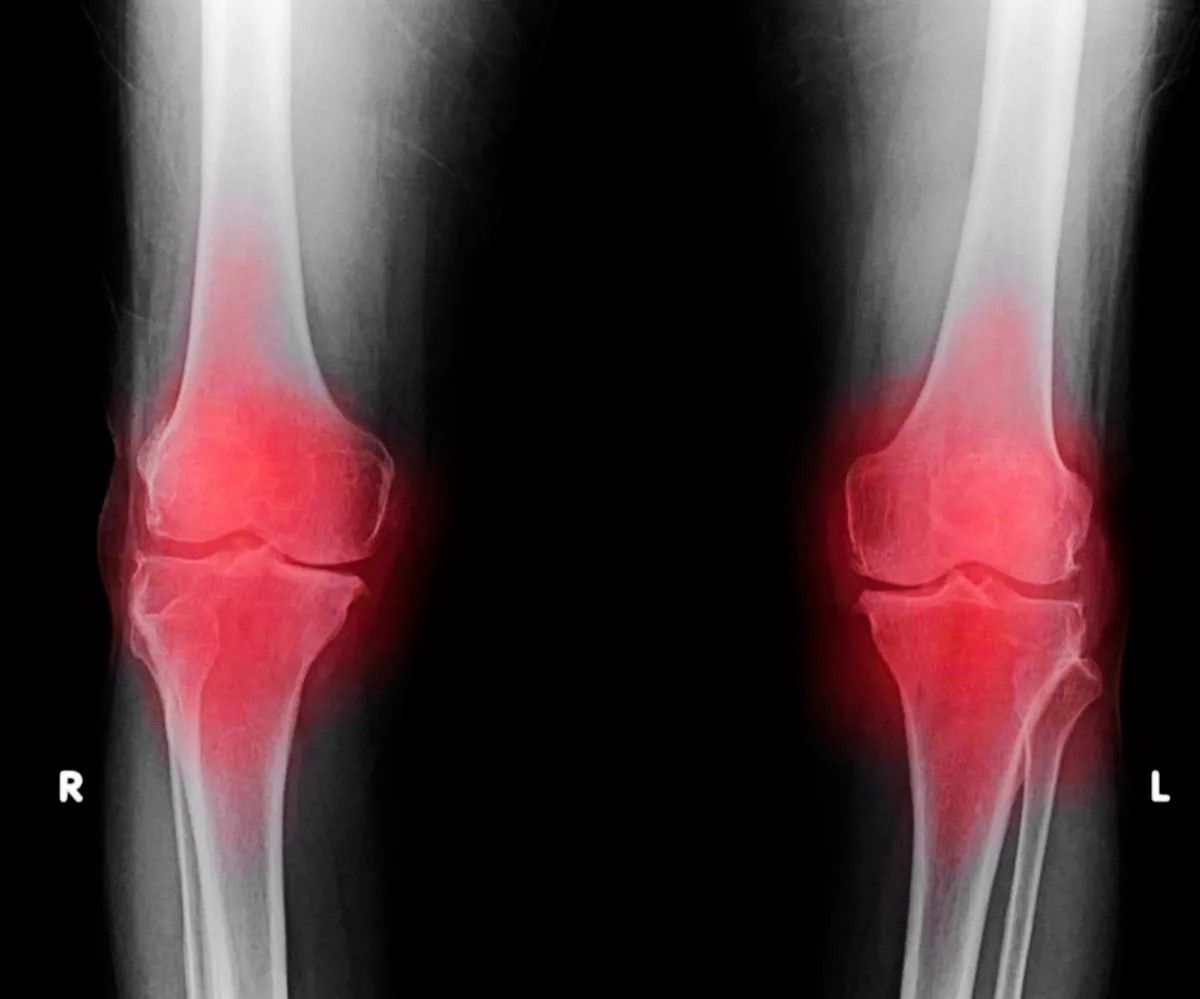

A tudomány világa új perspektívákat nyit a porckopás kezelésében. Az utóbbi években elért áttörések azt sugallják, hogy a jövőben az ízületpótló műtétek elkerülhetővé válhatnak. A kutatások célja a sérült szövetek újjáépítése és a fájdalom hatékonyabb enyhítése.

Az osteoarthritis jelenlegi kezelése leginkább a tünetek enyhítésére összpontosít, különösen a fájdalom csillapítására. A betegség okának kiküszöbölésére irányuló erőfeszítések eddig nem jártak sikerrel, így sokaknak csak a műtét jelenthet megoldást. A tudományos közösség azonban továbbra is keresi a betegség hatékony kezelésének módjait.